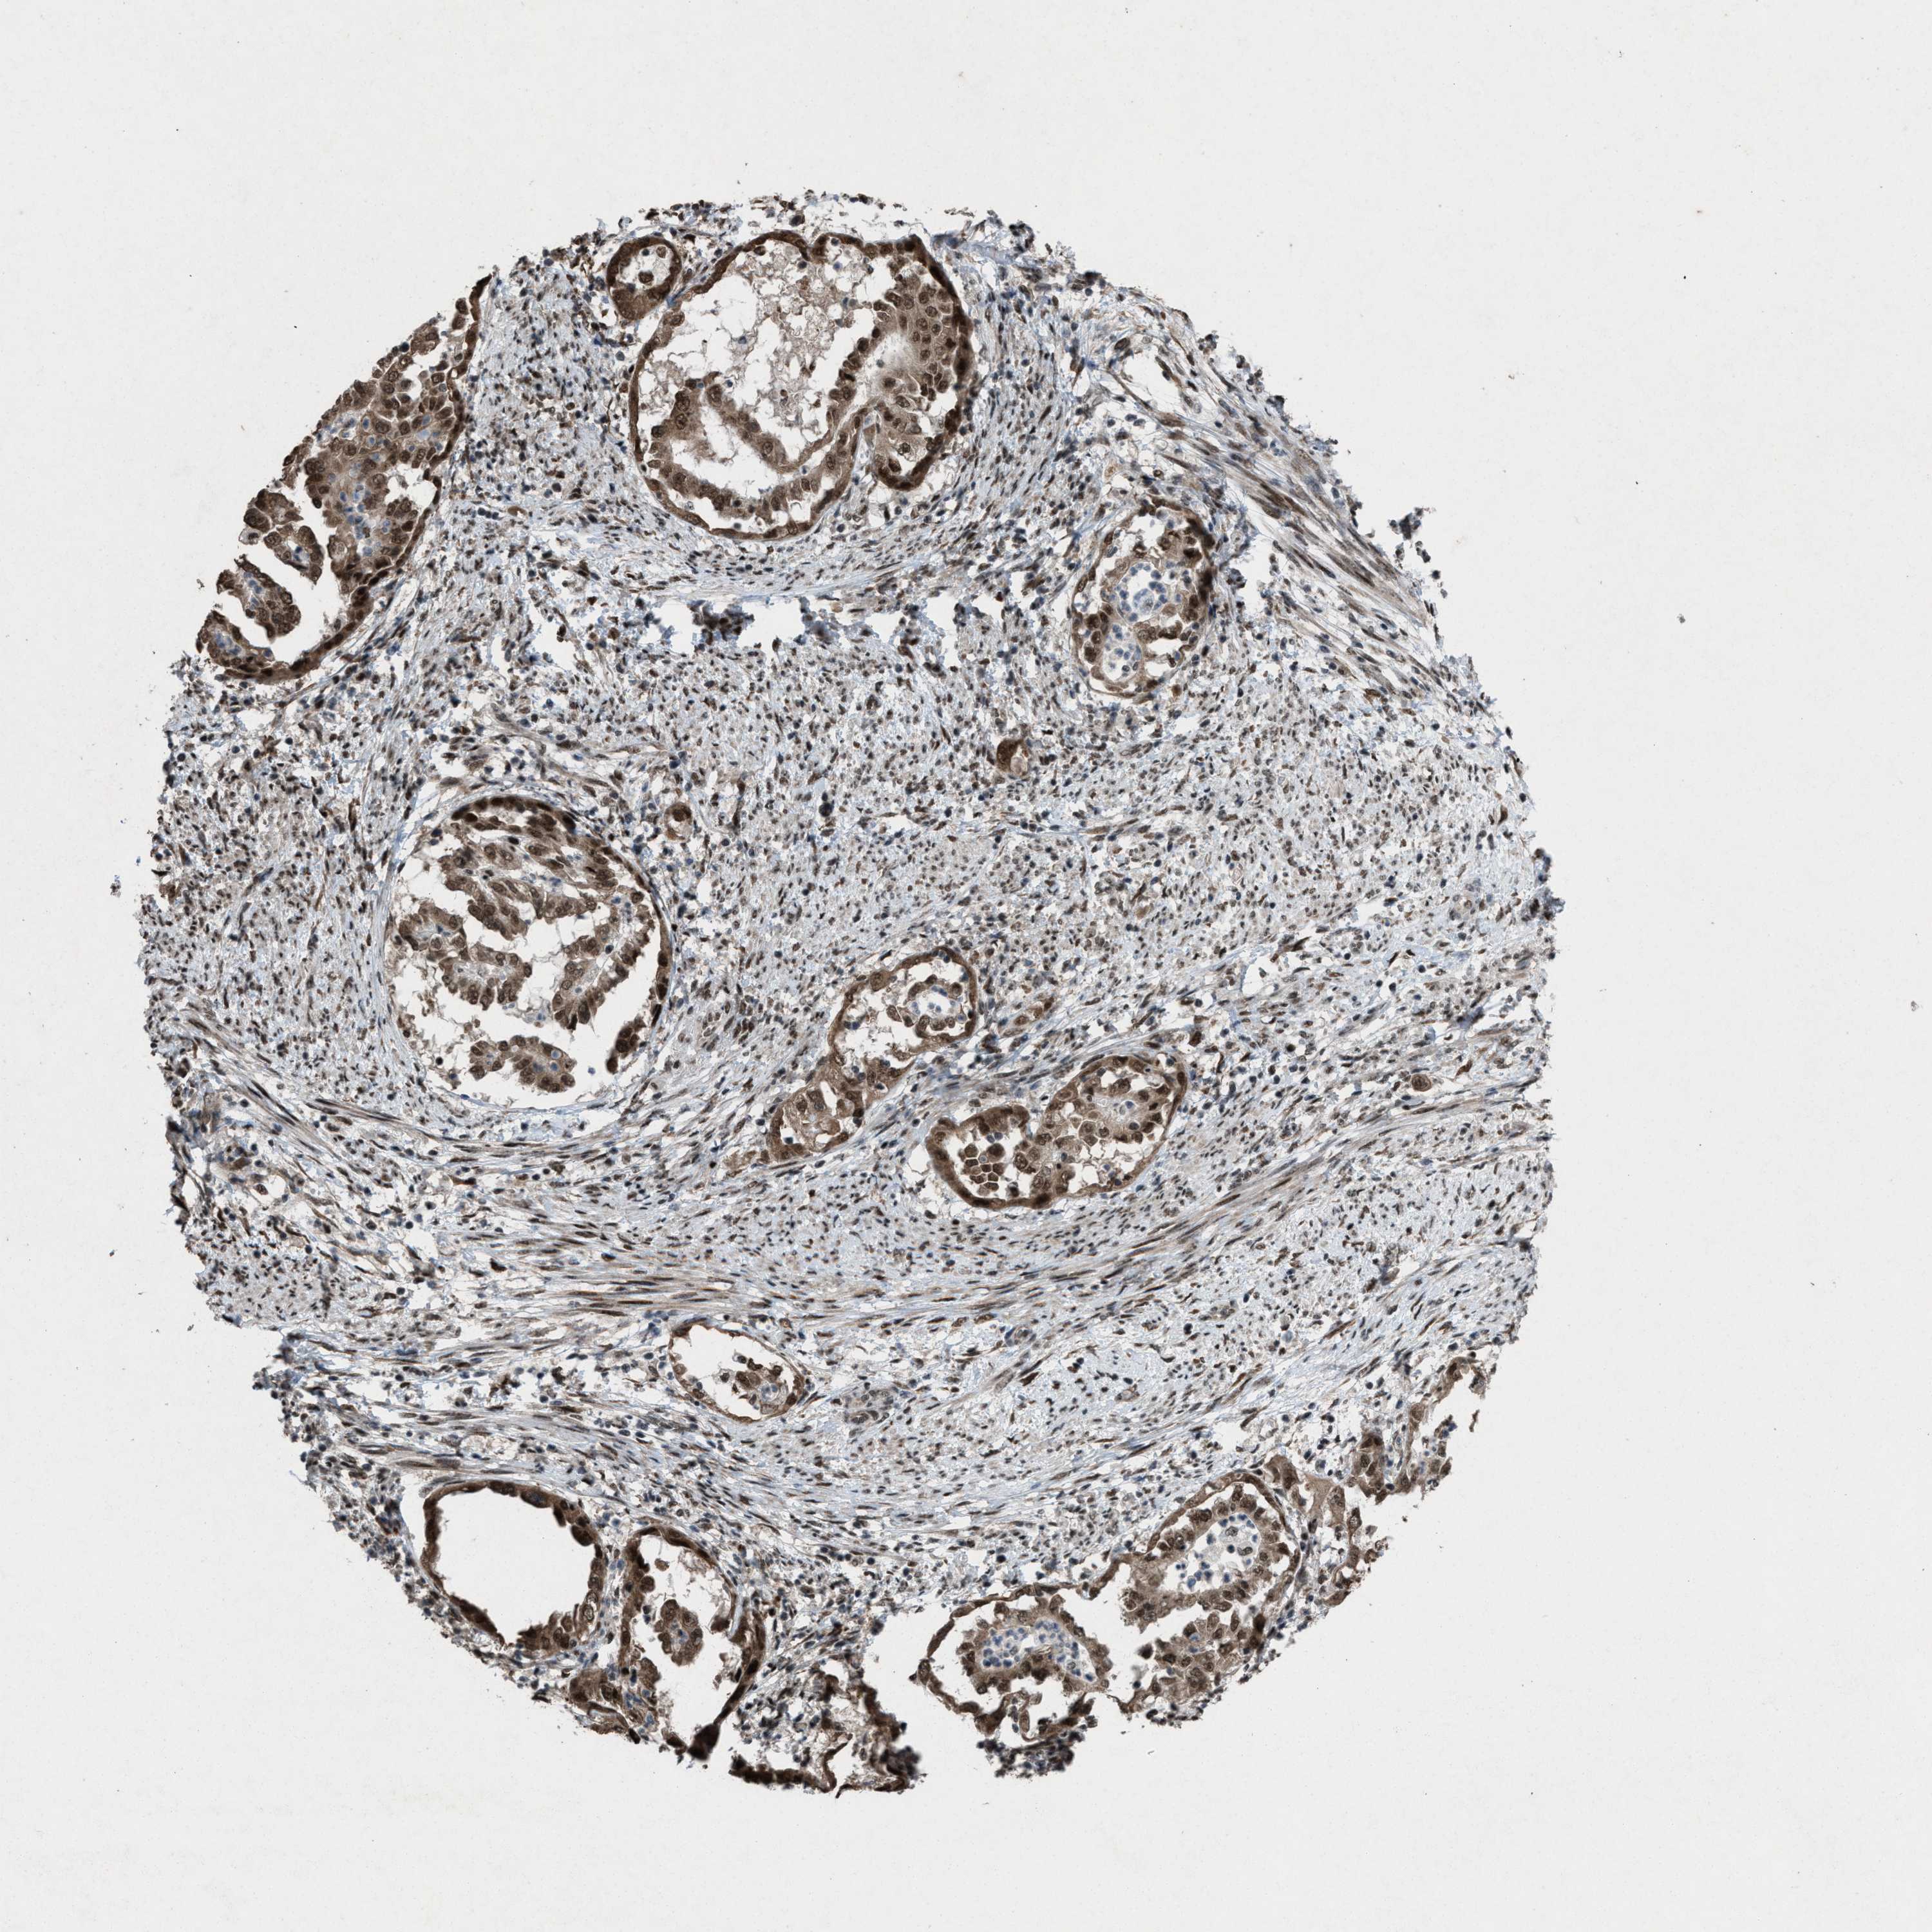

ENDOMETRIAL CANCER - Protein expressioni

A mouse-over function shows sample information and annotation data. Click on an image to view it in a full screen mode. Samples can be filtered based on level of antibody staining by selecting one or several of the following categories: high, medium, low and not detected. The assay and annotation is described here.

Note that samples used for immunohistochemistry by the Human Protein Atlas do not correspond to samples in the TCGA dataset.

Antibody stainingi

Antibody staining in the annotated cell types in the current human tissue is reported as not detected, low, medium, or high, based on conventional immunohistochemistry profiling in selected tissues. This score is based on the combination of the staining intensity and fraction of stained cells.

Each image is clickable and will lead to virtual microscopy that enables deeper exploration of all samples and also displays staining intensity scores, fraction scores and subcellular localization as well as patient and tissue information for each sample.

Antibody HPA021554

Staining

High

Medium

Low

Not detected

Intensity

Strong

Moderate

Weak

Negative

Quantity

>75%

75%-25%

<25%

None

Location

Nuclear

Cytoplasmic/membranous

Cytoplasmic/membranous,nuclear

Adenocarcinoma, NOS

Adenoma, NOS